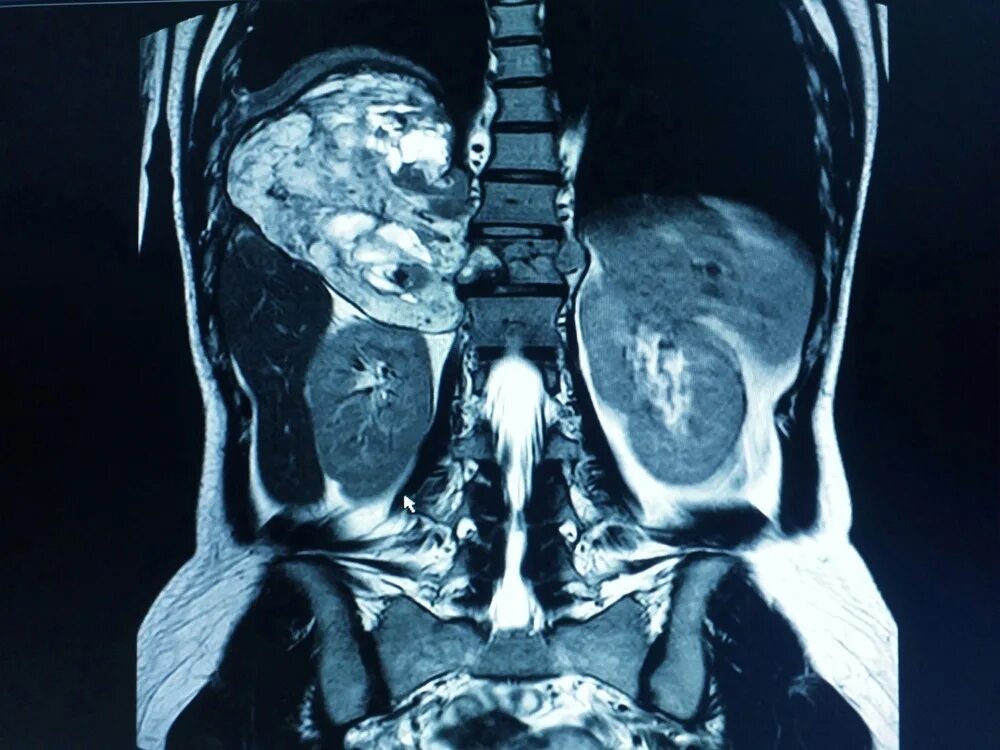

Что входит в мрт забрюшинного пространства